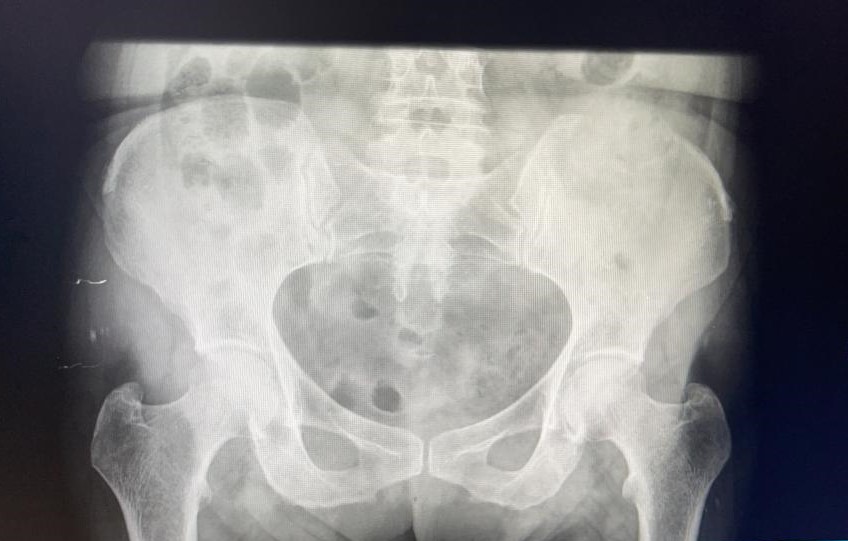

Rx pelvis: borrado de corticales en cresta ilíaca izquierda.

Coxalgia mecánica vs fractura pelvis vs metástasis ósea.

Se decide pedir ecografía reglada para valorar estudio posterior. Ecografía confirma sospecha de LOES intrahepáticas. Desde radiología amplian estudio con TAC: lesión ósea lítica con criterios de agresividad expansiva con masa de partes blandas en vertiente posterior de pala ilíaca izquierda.